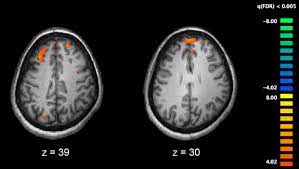

- 뇌의 구조 및 기능에 이상이 있는 것으로 보입니다. 조현병 환자들의 뇌 스캔 결과에서 뇌 부위의 크기나 활동에서 이상을 발견할 수 있습니다.

6. 신경생리학적 및 신경이미징 검사:

- 경우에 따라 뇌신경생리학적 검사, 신경영상학(예: 뇌 MRI 또는 CT 스캔) 등의 추가적인 검사가 필요할 수 있습니다. 이러한 검사는 다른 신체 질환을 배제하거나 뇌 구조 및 기능 이상을 확인하기 위해 시행될 수 있습니다.